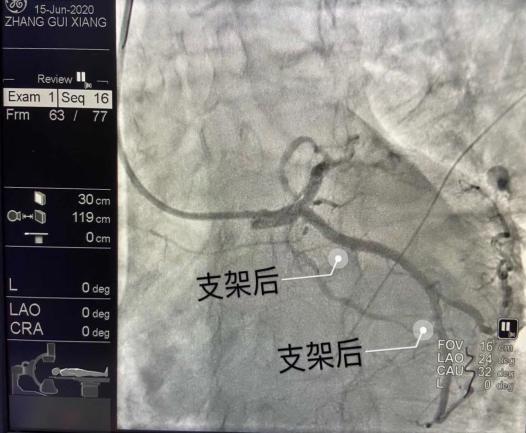

好在心内二科陈用贵团队对抢救这样的患者拥有着丰富的经验,他们在半小时内,于患者冠状动脉回旋支近段及远段共植入两枚支架,使患者症状明显缓解,术后生命体征平稳,安然返回病房。